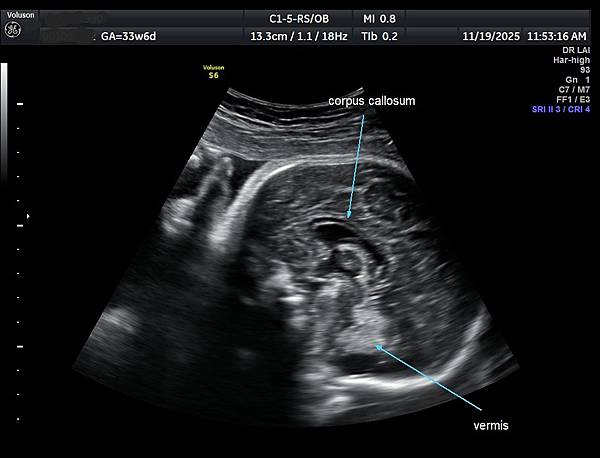

針對部分胼胝體發育不全的診斷,需要非常小心,如果胼胝體只有1/3的個案比較不會是假的,如果是2/3的個案就要很小心判斷是否過度診斷,我喜歡把胼胝體當做第五腦室(CSP )及第六腦室(cavum vergae )的天花板,CSP 與cavum vergae的比例大約2:1,通常CSP 和cavum vergae 都是黑黑的(附圖1),這樣的情況不會量錯,如果cavum vergae呈現白白時(echogenicity),它的天花板就很有可能被誤判不屬於胼胝體,這個問題我已經遇過很多類似的案例,例如附圖2~4是同一個case,圖4沒有疑慮,圖2及圖3很有可能只量到前面2/3比較明顯的部分,而沒有量到圖上的數據。